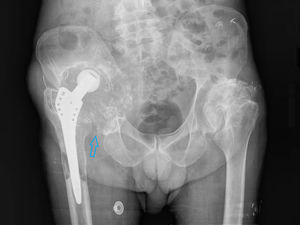

We present the case of a 66-year-old patient, recently diagnosed with bladder carcinoma after a haematuria study, with a picture of lameness and a painless right groin mass, of hard consistency on palpation. As personal background, we highlight a total right hip arthroplasty a few years ago due to severe osteoarthritis. The AP bilateral hip X-ray showed significant bone destruction of the right coxofemoral joint (Fig. 1). In light of these findings, an 18F-FDG PET CT was performed as an extension study of the primary bladder neoformative process, with the possibility of metastatic bone involvement. In the images at 60min post-injection of 18F-FDG a large mass of hypermetabolic multi-lobed soft tissue was observed in the right iliac region, which included the prosthetic material and produced lysis of the iliac wing, with significant destruction of the coxofemoral joint (Fig. 2). A biopsy was performed in view of the findings indicating malignancy, the result was particle disease due to wear and tear of the arthroplasty components. The patient refused surgical revision and is currently undergoing regular follow-up.

The particles produced by the friction mechanism of the prosthesis migrate to the prosthesis-bone interface and produce a biological response that causes linear or rounded areas of osteolysis, similar to tumour or infectious processes, leading to loosening and displacement of the prosthesis.1 Macrophages are the cells responsible for the recognition of these particles and the production of pro-inflammatory cytokines that lead to the activation of osteoclasts, which are responsible for periprosthetic bone resorption. This hyperosteoclastogenesis induced by joint implant degeneration products constitutes the most common mechanism of failure of arthroplasties after 10 years, with few cases before this time.2,3 Radiographic evidence of periprosthetic bone loss is a slow process and infrequent under 5 years following implantation. Therefore, it is recommended that patients are periodically evaluated by radiological study (especially at 5–8 years) to rule out subclinical periprosthetic osteolysis.3 It is essential to know the physiopathology and morphological-functional characteristics of this entity, which produces a local inflammatory state that is difficult to distinguish from aggressive processes.1–3